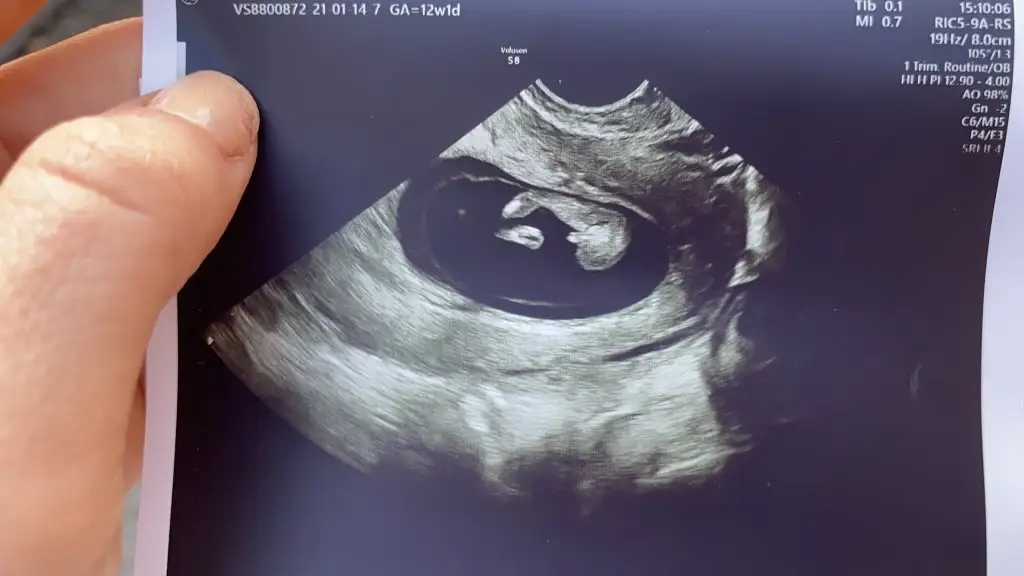

Sana yazacaktım msjı bulamadım benim yorumum bebek erkek nub teorisinde çıkıntı yukardaArkadaşlar 12. Haftada detaylı ultrasonda doktorum erkek dedi genitalin resminide çekti 14. Haftamdayım başka bir doktor kemik yapısına göre kız dedi tecrübeli arkadaşlar bakabilir mişne olsa bizim ama merak resimler 12 ve 14 hafta resimleri

Hissiyat ama erkek diyorumArkadaşlar 12. Haftada detaylı ultrasonda doktorum erkek dedi genitalin resminide çekti 14. Haftamdayım başka bir doktor kemik yapısına göre kız dedi tecrübeli arkadaşlar bakabilir mişne olsa bizim ama merak resimler 12 ve 14 hafta resimleri

Bana da bakar mısın lütfeeeen 13 ve 16 haftalıkSana yazacaktım msjı bulamadım benim yorumum bebek erkek nub teorisinde çıkıntı yukarda